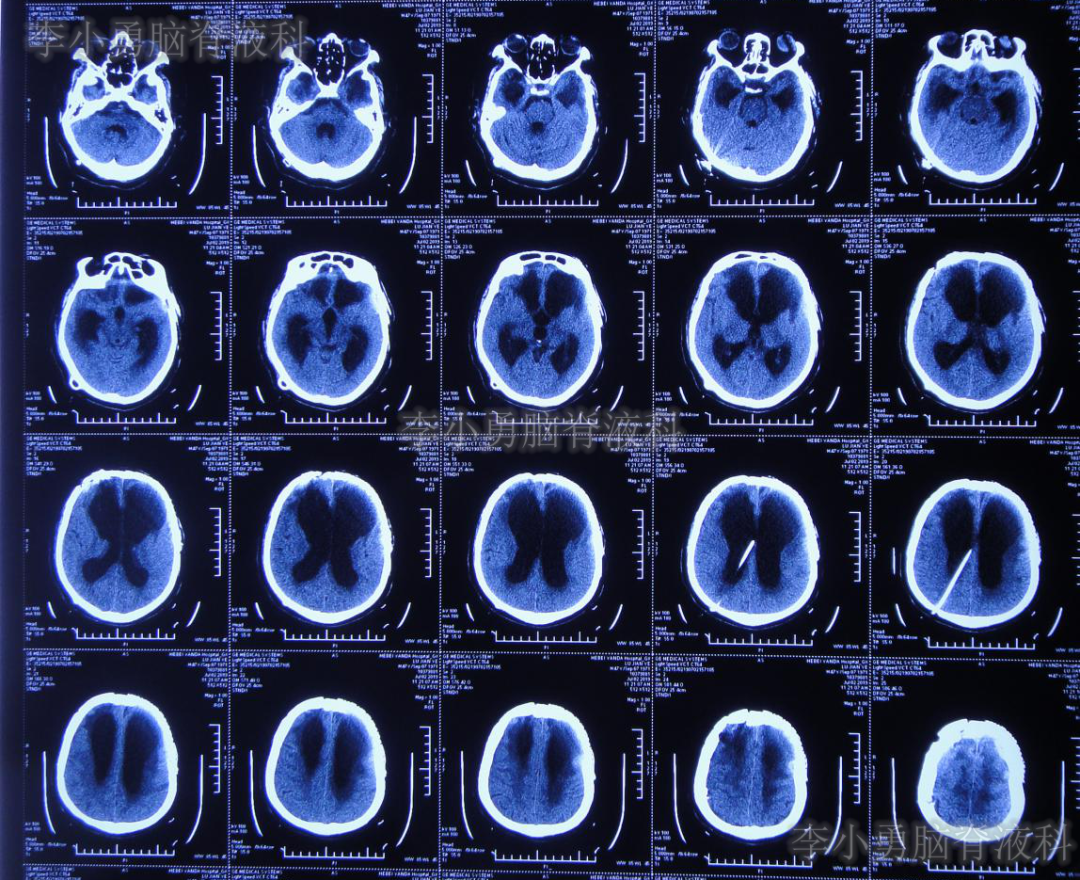

2019年3月12日即开颅术后71天,从山西太原转至北京某三甲医院;住院时复查头颅CT(图-2)示双侧侧脑室扩张,右侧硬膜下积液并少量出血,减压窗处脑膜脑膨出。

图-2:2019年3月12日头颅CT

入院1周后即2019年03月19日即开颅术后78天,进行了左侧额部颅骨缺损钛板修补术+脑室腹腔分流术。术后当天复查头颅CT(图-3)示右侧脑室内可见分流管,左侧颅骨修补术后改变,但右侧仍有硬膜下积液合并出血。

图-3:2019年3月19日头颅CT

颅骨修补及脑室腹腔分流术后1周即2019年3月27日即开颅术后86天,从第2家医院直接转回第1次开颅手术的山西省某三甲医院康复科,行康复治疗;但入院当天即出现高热39.2℃,以及恶心、呕吐症状。行胸部CT,抽血化验等检查及头颅CT(图-4)后,认为均无明显异常。

图-4:2019年3月27日头颅CT

在山西三甲医院治疗13天后,于2019年4月9日即颅骨修补术+脑室-腹腔分流术后21天,再次转回北京某三甲医院。入院当天复查头颅CT(图-5)示脑室引流术后状态。

图-5:2019年4月9日头颅CT

2019年4月22日即脑室-腹腔分流术后34天,第3家医院住院第2天再次出现发热38.6℃,并行头颅CT(图-6)检查示仍为脑室引流术后状态;但胸部CT(图-7)检查示肺炎。

图-6:2019年4月23日头颅CT

虽然已显示出脑积水加重的表现,但医生仍考虑发热为肺部感染引起,因此给予抗菌素治疗2月余。但发热仍难以控制,并且患者意识也逐渐恶化至昏迷的状态,肢体活动亦明显减少。2019年7月2日(颅骨修补术+脑室-腹腔分流术后105天)复查头颅CT(图-8)示脑室进一步扩大。无奈此时再次给予腰椎穿刺,但脑脊液化验仍不支持“颅内感染”。

图-8:2019年7月2日头颅CT